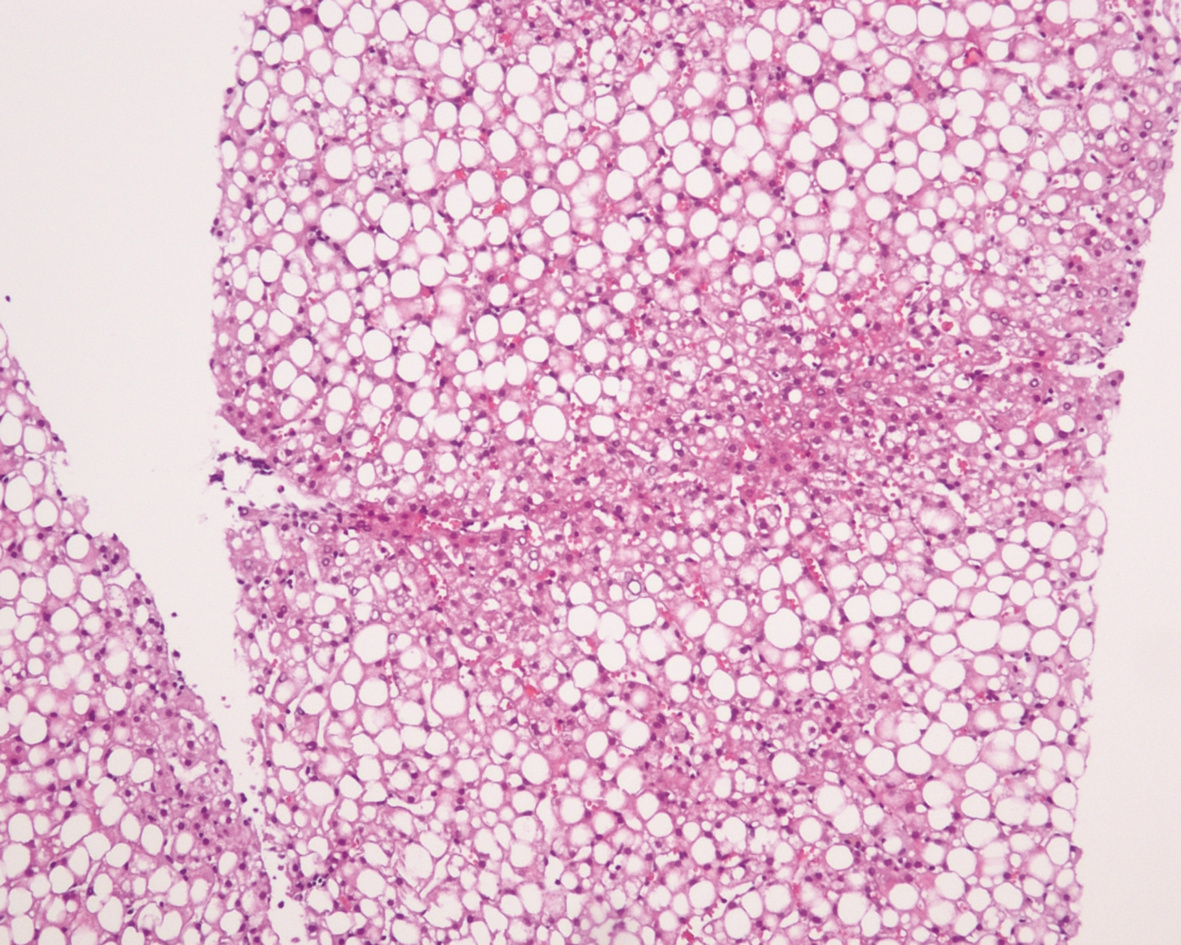

10例儿童肝糖原累积病临床及病理学分析

赵素贤, 刘世恒, 李文聪, 韩芳, 刘树红, 张庆山, 任伟光, 孔令波, 付娜, 王荣琦, 孔丽, 南月敏, 赵景民

2022, 38(8): 1839-1842. DOI: 10.3969/j.issn.1001-5256.2022.08.022

摘要(1407) HTML (512) PDF (2394KB)(109)

摘要:

目的  探讨儿童糖原累积病(GSD)的临床及病理学特点。  方法  选择2002年1月—2022年1月河北医科大学第三医院及解放军第五医学中心经病史、肝脏生化及肝活组织检查确诊的GSD 10例,对比分析人群特征、临床表现、生化指标、肝组织病理学特点。  结果  10例患儿发育迟缓,矮小,均表现为肝功能异常,轻度乏力、纳差、尿黄、眼黄,4例患者肝脾肿大。6例患者有低血糖的临床表现;1例患儿双侧腓肠肌肥大,Gower征阳性。2例患儿巨细胞病毒IgG阳性。肝组织病理学表现肝细胞弥漫性肿大,胞浆空淡,核小居中似植物细胞状,伴或不伴纤维组织增生。  结论  GSD患者多数有发育迟缓、转氨酶异常,肝组织病理检查有其特异性病理特征。